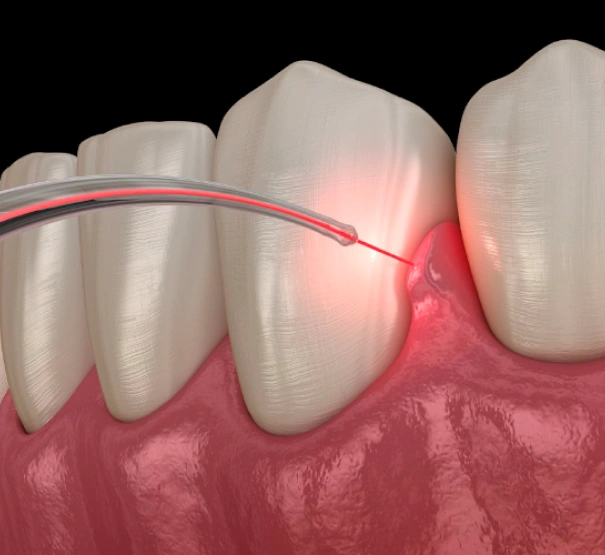

Your gum care may include a deep cleaning procedure called scaling and root planning. This process removes plaque and tartar from below the gum line and smooths the root surfaces of your teeth to help your gums reattach and heal.